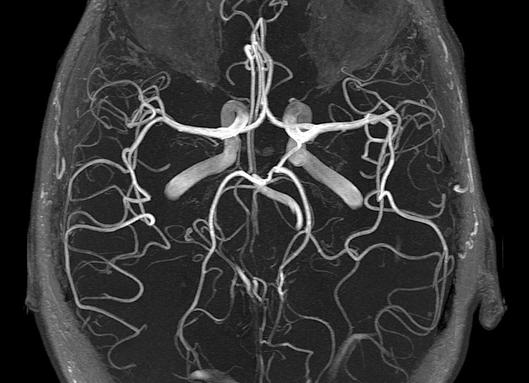

Назначили магнитно-резонансное исследование, но придя домой Вы вспомнили о некоторых противопоказаниях процедуры и о том, что у Вас установлен искусственный зуб? А можно ли делать МРТ с имплантами зубов? Давайте разберёмся. Теоретически магнитное воздействие влияет на металл, и штифт имплантата может изменить положение. В некоторых фильмах Вы могли видеть, как с кожи сдирало татуировки, в чернилах которых содержался металлический компонент. Если бы всё действительно было так страшно, в кабинете врача должны были бы висеть огромные яркие таблички с предупреждением об этом, не так ли? Из физики мы знаем, что некоторые типы металлов при нагревании начинают смещаться. Современные имплантационные системы содержат безопасные, биосовместимые ингредиенты. Точный состав Вашего имплантата стоит уточнить у стоматологов. Достаточно будет вспомнить название системы. Чаще всего это титан. МРТ с имплантами зубов из титана не поддаются деформациям. Магнитное поле томографа устроено так, что смещению поддаются только незафиксированные части, а имплантат прочно зафиксирован в десне. Однако стоит учесть, что мрт головного мозга с имплантами зубов могут давать неточную картину. Конструкция может создавать фон, и портить изображение. Из-за этого неосведомлённый доктор может поставить неправильный диагноз. В случае же с другими частями тела – всё в порядке. Наличие имплантата никак не скажется на результатах.